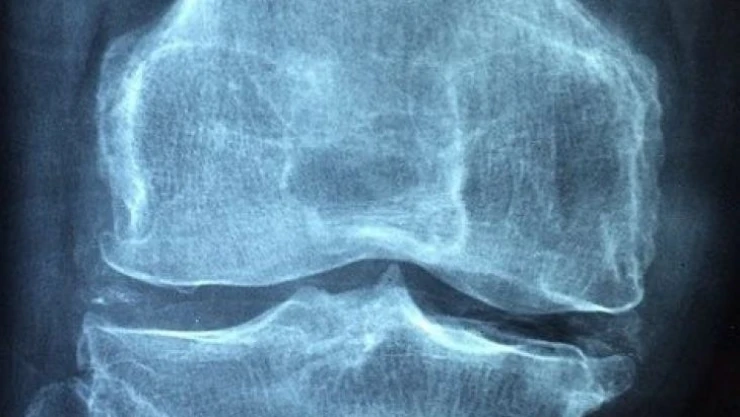

Medipol Mega Üniversite Hastanesi Ortopedi ve Travmatoloji Bölümü Başkanı Prof. Dr. İbrahim Azboy, diz ve kalça protezleri ameliyatlarından sonra karşılaşılan komplikasyonların başında gelen protez enfeksiyonlarının önlenmesi ve tedavisi ile ilgili bilgiler verdi. Prof. Dr. Azboy, günümüzde yaşlı nüfusun artmasına paralel olarak diz ve kalça kireçlenmelerinde ciddi artış görüldüğünü belirterek, “Buna bağlı olarak diz ve kalça protezi ameliyatları her geçen gün daha yüksek sayılarda uygulanmaktadır. Diz ve kalça eklem protezleri hastaların yaşam kalitelerine ciddi anlamda katkı sunan başarılı ameliyatlardır. Ancak bu ameliyatların önemli komplikasyonlarından birisi de protez enfeksiyonudur. Yüzde 2 civarında görülen bu komplikasyon hastayı ve hekimi ciddi anlamda yoran ve sağlık sistemine ciddi maliyetler getiren önemli bir durumdur. Protez enfeksiyonu ile mücadele etmek zordur. Tedavi için bazen birkaç ameliyat gerekmektedir. Uzun süre hastalar antibiyotik tedavisi kullanmak zorunda kalmaktadır” diye konuştu.